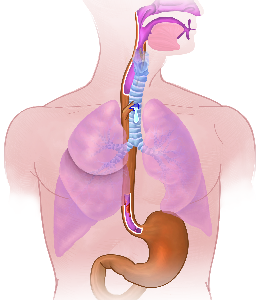

Detailreiche Fotografien aus der medizinischen Praxis ergänzen die Texte; moderne, genaue,

wissenschaftliche Zeichnungen geben Einblick in die Anatomie und die Funktion der Lunge und

anderer Organe.